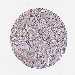

LIVER CANCER - Protein expressioni

A mouse-over function shows sample information and annotation data. Click on an image to view it in a full screen mode. Samples can be filtered based on level of antibody staining by selecting one or several of the following categories: high, medium, low and not detected. The assay and annotation is described here.

Note that samples used for immunohistochemistry by the Human Protein Atlas do not correspond to samples in the TCGA dataset.

Antibody stainingi

Antibody staining in the annotated cell types in the current human tissue is reported as not detected, low, medium, or high, based on conventional immunohistochemistry profiling in selected tissues. This score is based on the combination of the staining intensity and fraction of stained cells.

Each image is clickable and will lead to virtual microscopy that enables deeper exploration of all samples and also displays staining intensity scores, fraction scores and subcellular localization as well as patient and tissue information for each sample.

Antibody HPA054422

Antibody HPA060360

Staining

High

Medium

Low

Not detected

Intensity

Strong

Moderate

Weak

Negative

Quantity

>75%

75%-25%

<25%

None

Location

Nuclear

Cytoplasmic/membranous

Cytoplasmic/membranous,nuclear

Carcinoma, Hepatocellular, NOS

Cholangiocarcinoma